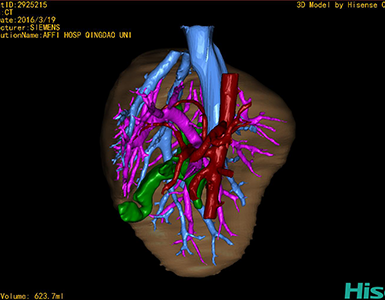

CT结果输入海信CAS系统后行3D重建及手术规划后,于2016-3-22全麻下行“胆总管囊肿切除+胆囊切除+胆总管-空肠吻合术”手术治疗:

术前三维重建及手术方案设计:

将0.625mm双源薄层CT资料的静脉期和动脉期Dicom格式文件导入海信CAS系统。

通过调节窗宽窗位调整CT序号,对肝实质,胆囊,下腔静脉,肿瘤,肝动脉、门静脉及肝静脉等进行三维重建;系统自动计算肝脏体积。

术前手术方案的规划。

术前三维重建:

重建图片